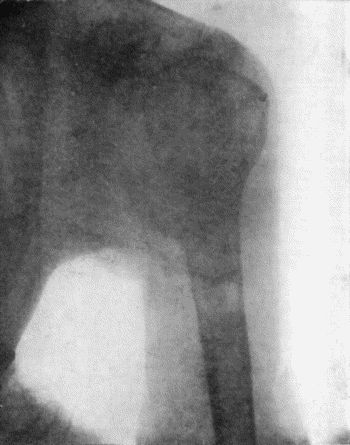

137.Radiogram of Upper End of Femur in Osteomyelitis Fibrosa 478

42.Tertiary Syphilitic Ulceration in region of Knee and on both Thumbs 171